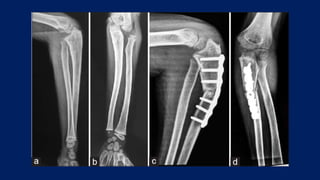

CASE DISCUSSION

• 7 year old child

July 2021 Xray

CASE DISCUSSION • 7year old child July 2021 Xray